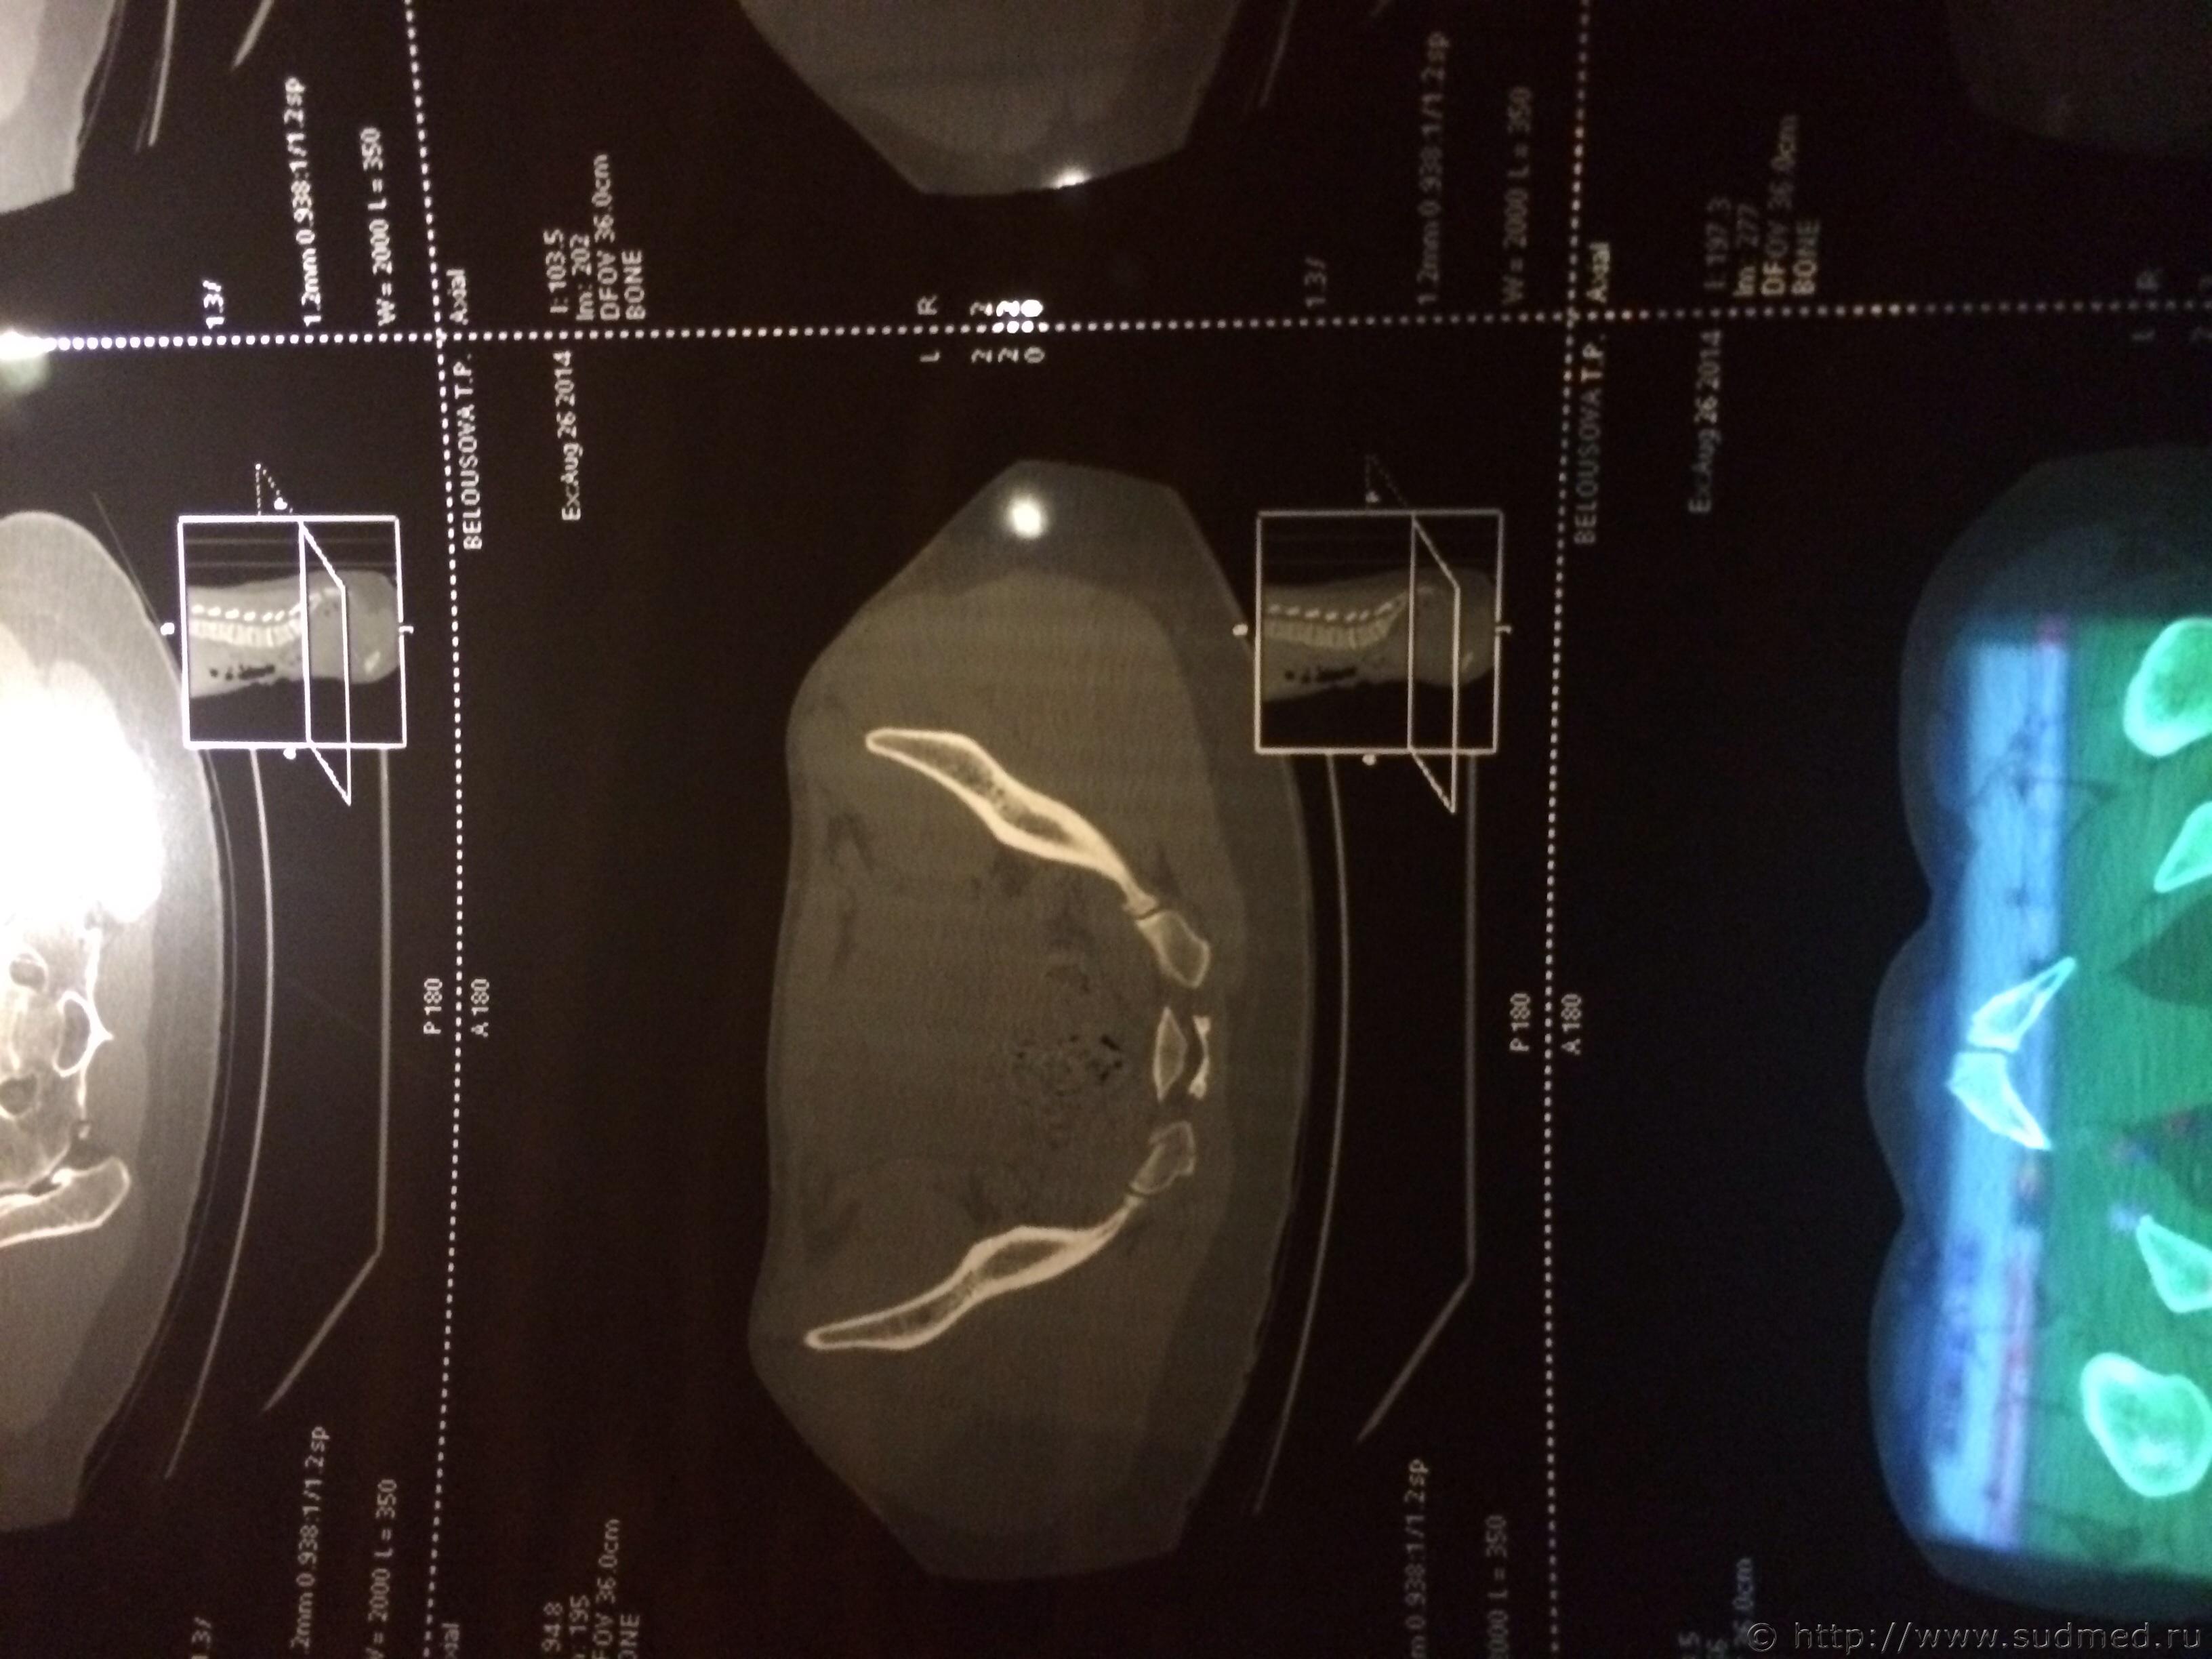

Спасибо! У меня результаты КТ, ошиблась)

КТ

Как мне видится - вертикальный перелом крестца. Тяжкий вред.

Впрочем, оставляю небольшую вероятность, что я не видел все сканы, да и качество их здесь, разумеется, хуже, чем изображение на пленке или на экране компьютера у врача, работающего на томографе.